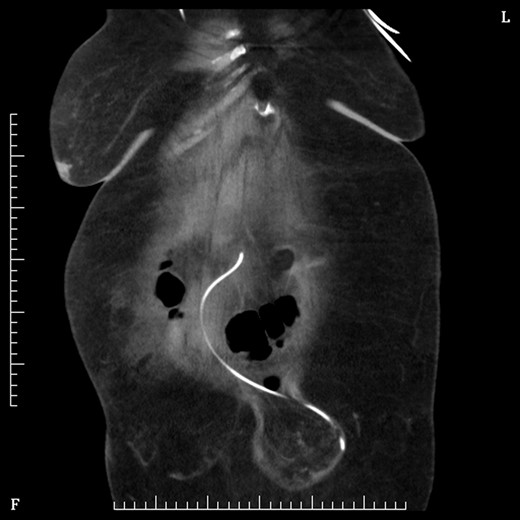

On Day 2 post VP shunt insertion, she was noted to be slow to recover and CT abdomen was performed. This demonstrated that the distal catheter tip was not in the pleural space but entered the abdomen and was redirected out along a tract into an umbilical hernia (Fig. 5). The following day she was taken back to theatre and the VP shunt was revised, and good visualization into the abdomen gave the impression that it was correctly in place. Repeat CT abdomen was performed to confirm placement and to our surprise the catheter had re-entered the same tract and travelled into the umbilical hernia (Fig. 6).

Coronal section CT abdomen after second shunt revision showing catheter again protruding out through umbilicus into hernia sac.